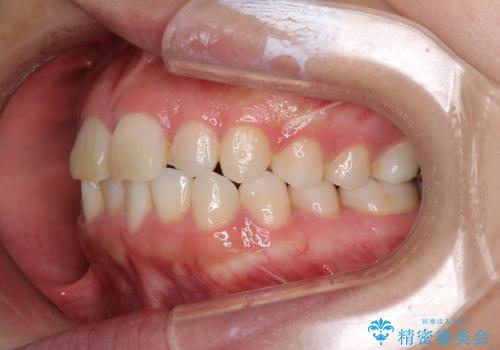

- ワイヤーではない矯正治療があると聞いたとのことで来院された患者様です。

長年前歯のデコボコを気にしていたもののワイヤー矯正に抵抗があり躊躇していたそうですが、インビザラインなら治療してみたいとのことで相談にいらっしゃいました。

インビザライン適用の歯列であったため、歯と歯の間を削るIPRを用いて改善することとしました。

お仕事柄、長時間のマウスピース装着が苦ではなかったので、歯列はすぐに整いましたが、ゆっくりとした交換頻度であったので、2年ほどの治療期間を要しました。